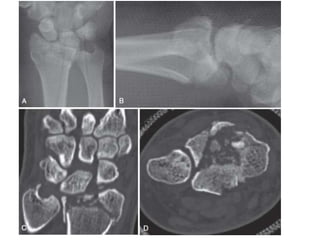

Diagnóstico: Radiológico

RX AP + LATERAL

TAC

Fracturas intrarticulares

Detectar hundimientos

No congruencia

Lesiones asociadas.

Diagnóstico: Radiológico RX AP+ LATERAL AP Acortamiento radial Inclinación radial 23 grados Desplazamiento Radial Plano Sagital Inclinación Radial Desplazamiento TAC Fracturas intrarticulares Detectar hundimientos No congruencia Lesiones asociadas. RMN Lesiones ligamentares Fx Escafoides.